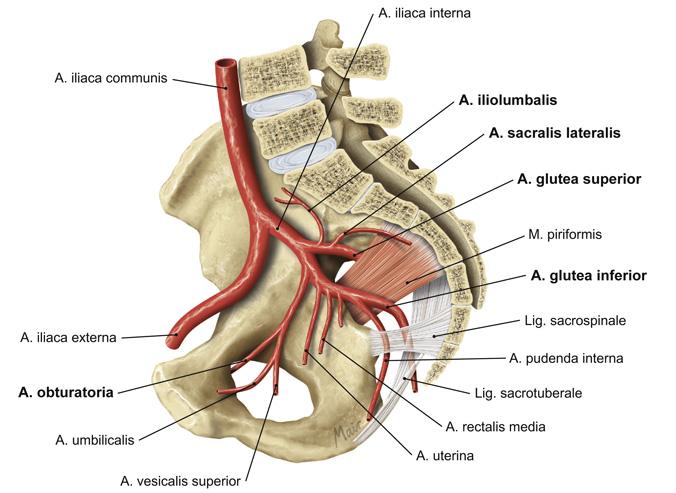

Fig 3.27: a. iliaca interna - dorsale hoofdstam

A doorsnede

os pubis sacrum -

a iliolumbalis

a sacralis lateralis -

a glutea superior

r superficialis r profundus

B vooraanzicht

C zijaanzicht

os coxae > os ilium lig sacrotuberale -

lig sacrospinale